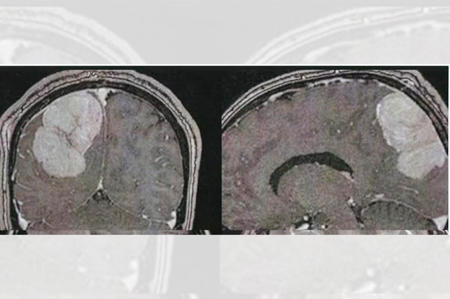

عرب معتمر کی کھوپڑی میں رسولی

مدینہ منورہ ۔۔۔ یہاں کنگ فہد جنرل اسپتال کے ماتحت دماغ اور اعصاب کے جراحوں نے ایک عرب ملک کے 44سالہ معتمر کی کھوپڑی سے آپریشن کرکے رسولی نکال دی۔ تفصیلات کے مطابق ڈاکٹر محمد عبد الرحیم نے آپریشن کی قیادت کی۔ عرب معتمر کو اسپتال لایا گیا تھا۔ وہ مسلسل درد سر کی شکایت کررہا تھا۔ جسم کے بائیں حصے میں کمزوری اور نظر میں کمی کا بھی شاکی تھا۔ ایکسرے کئے گئے تو پتہ چلا کہ اس کی کھوپڑی میں ایک بڑی سی رسولی بنی ہوئی ہے اور وہ دماغ پر دباﺅ ڈال رہی ہے۔ آپریشن کا فیصلہ کیاگیا۔ 8گھنٹے طویل آپریشن رہا۔ بالاخر کامیاب رہا۔ اب عرب معتمر کی حالت بہتر ہے۔